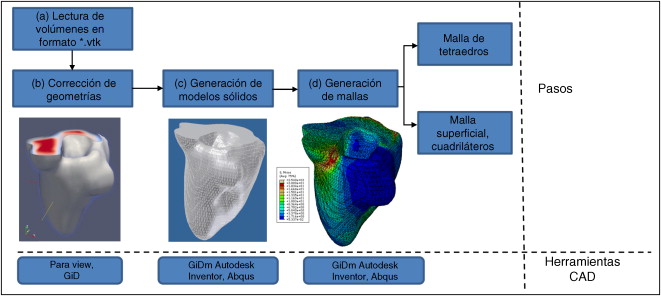

El problema de obtener modelos geométricos a partir de imágenes médicas implica la utilización de un conjunto de rutinas de procesamiento aplicadas a la matriz 3D de las imágenes médicas a lo largo de varias etapas de procesamiento. En la figura 1 se observan las cinco etapas propuestas con las herramientas de software utilizadas en cada una de ellas, las cuales son: (1) etapa de lectura y reconstrucción, en la cual se implementó una rutina para obtener una imagen 3D de dimensiones m × n × o obtenida por el apilamiento paralelo de o cortes ortogonales (axial, coronal o sagital) del mismo tamaño de m × n pixels , donde cada elemento de la matriz representa un valor de intensidad de gris calculado por la interacción de la radiación en el tejido. (2) Preproceso, en la cual se aplicaron rutinas de suavizado de ruido y realzado de bordes, de este modo se mejoró la calidad de las imágenes, preparándolas para la siguiente etapa. (3) Segmentación, en la cual se utilizaron rutinas de extracción del volumen de los tejidos u órganos de interés. (4) Remuestreo, donde se emplearon rutinas de posprocesamiento para suavizar las superficies y eliminar elementos no conectados presentes en los volúmenes segmentados. (5) Exportación de modelos, para lo cual se implementaron rutinas para almacenar los volúmenes obtenidos en formatos legibles por herramientas de visualización médica y CAD, en las cuales se visualice en sólidos, superficies, mallas, etc.

Figura 1. Esquema de procesos y rutinas implementados en una herramienta de procesamiento de imágenes médicas desarrollada en MATLAB [13] . |

Para procesar los modelos geométricos en otras herramientas de visualización médica y CAD, se implementó una rutina de exportación de la data de los volúmenes en formatos *.vtk[33] que permite guardar las coordenadas de los voxels y el tamaño de ellos en las direcciones x , y, z y en formato *.stl[34] que almacena una malla de triángulos sobre las superficies para definir la forma del objeto. Este es un formato de salida estándar para la mayor parte de los programas CAD. Utilizamos GiD [35] y ParaView [36] para visualizar los modelos en superficie y generar el mallado. Se empleó Autodesk Inventor [37] para convertir los modelos en sólidos y finalmente, se utilizó Abaqus [38] para discretizar los modelos y hacer análisis con elementos finitos.

Se emplearon las herramientas Abaqus y Autodesk Inventor para leer los archivos generados y verificar si los modelos geométricos obtenidos con la metodología eran útiles para discretizar, para ello se asignaron valores de contorno de prueba en diferentes zonas del volumen sólido de los modelos.